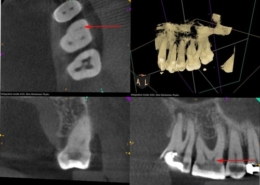

Tehnike pronalaska sekundarnog meziobukalnog kanala

Oblik obrisa pristupnog kaviteta prvog gornjeg kutnjaka trokutast je i smješten u mezijalnoj polovici zuba s osnovom prema bukalno i vrhom prema lingvalno (Slika 3.). Meziobukalni korijen vrlo je širok u bukolingvalnom smjeru, tako da je česta pojava manjeg sekundarnog meziobukalnog kanala. [8] Dno pulpne komore ima određena morfološka obilježja koja su od velike pomoći pri traženju kanala. Obično su na dnu vidljive linije koje vode prema ulazima u kanale i tvore zamišljenu „mapu“, odnosno rostrum canalis. [1] Primarni meziobukalni kanal smješten je blago distalno u odnosu na vrh meziobukalne kvržice, dok je manji sekundarni meziobukalni kanal smješten mezijalno od zamišljene linije koja povezuje primarni meziobukalni i palatinalni kanal, približno na udaljenosti 1 do 3 mm od primarnog. [4] Sam ulaz u sekundarni meziobukalni kanal teško je uočljiv kliničkom inspekcijom zbog dentinskog ramena koje ga pokriva i koje je potrebno ukloniti za lakši pristup kanalu. Osim dentinskog ramena, problem je i meziobukalni nagib ulaza te nagla zavijenost kanala u koronarnoj trećini prema mezijalno što ukazuje na najjednostavniji pristup iz distopalatinalnog kuta. [10] Upravo iz navedenih razloga, kako bi se poboljšala sama pristupačnost kanalu, potrebna je početna priprema i modifikacija pristupnog kaviteta u romboidni oblik uz oprez i minimalnu invazivnost. Istraživanjem je dokazano da je uklanjanje dentina s dna pulpne komore (tzv. troughing) do 2 mm od palatinalnog prema primarnom meziobukalnom kanalu korisna metoda te da su njezine prednosti nadmašile rizik od perforacije. [1] Potrebna je i dobra vizualizacija dna pulpne komore za što se koristi mikroskop, lupe ili barem intraoralno ogledalo s prednjom reflektirajućom površinom. Uz dobru pristupačnost i vizualizaciju lakše je istraživanje dna pulpne komore i traženje ulaza u kanal. Instrumenti poput DG16 Explorer (Slika 4.) ili tanki instrument poput D finder #10 (Slika 5.) od velikog su značaja za lociranje kanala. Iznimno su korisni i ultrazvučni instrumenti koji selektivno uklanjaju kalcifikacije u pulpi i čuvaju dentin od pretjerane štete te otkrivaju skriveni ulaz u kanal. Važno ih je pažljivo koristiti, laganim, kontroliranim pokretima kako bi se izbjeglo pretjerano uklanjanje dentina i iatrogena perforacija. Kod samog traženja kanala, irigacija može pomoći u njihovoj lokalizaciji. Natrijev hipoklorit ima antimikrobna svojstva, osigurava bolju vidljivost, smanjuje rizik od kontaminacije, omogućuje lakši pristup instrumentima te uklanja ostatke organskog materijala. Pulpni ostaci mogu reagirati s natrijevim hipokloritom pri čemu se stvaraju mjehurići, odnosno dolazi do stvaranja kisika, što je pokazatelj položaja ulaza u kanal te potencijalnog postojanja novih, neotkrivenih kanala. Uz natrijev hipoklorit, kao dijagnostičko sredstvo za lociranje kanala upotrebljava se i kemijski spoj 1% natrijev fluorescein. To je oftalmološka otopina koja ima svojstvo vezanja za vezivno tkivo i svijetli kada se izloži plavom svjetlu. Nalapatti i Glassmann predložili su njegovu upotrebu, na način da se otopina aplicira u pulpnu komoru i ostavi da djeluje i reagira 2 minute. [1] Aplikaciju je potrebno obaviti oprezno i paziti na određeni vremenski interval djelovanja, budući da postoji rizik od obojenja zuba. Nakon toga potrebno ju je izložiti plavom polimerizacijskom svjetlu, a kanale promatrati mikroskopom. Važno je obilno isprati pulpnu komoru natrijevim hipokloritom nakon završenog postupka. Na temelju te tehnike, napravljen je i veliki pomak u razvitku mikroskopa, odnosno kobaltno-plavog filtra koji omogućuje još precizniju i jednostavniju primjenu natrijevog fluoresceina. [1] Još jedan vrijedan dijagnostički alat, koji nam omogućuje trodimenzionalan prikaz anatomije jest CBCT (konusna kompjutorizirana tomografija). Ova tehnologija omogućuje bolju vizualizaciju, prepoznavanje varijacija, planiranje samog pristupa, minimalno invazivnu preparaciju te veću predvidivost terapije (Slika 6.). Kliničkom studijom dokazano je da je učinkovitost korištenja CBCT-a u pronalaženju dodatnih sekundarnih meziobukalnih kanala u maksilarnim kutnjacima ograničena te je sam kanal bio prikazan u 33 % slučajeva. [11]